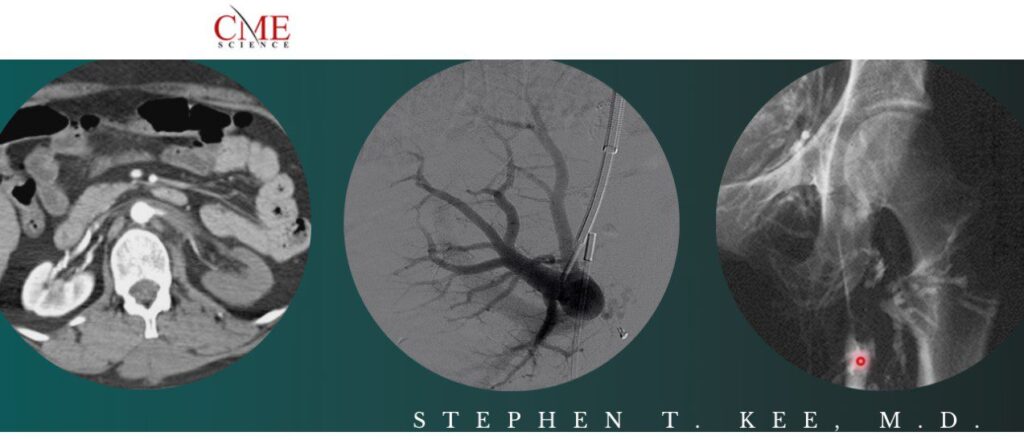

- Uterine Interventions(37:15)

- Peripheral Aterial Disease(54:27)

- Portal Hypertension(46:53)

- Prostatic Artery Embolization(34:06)